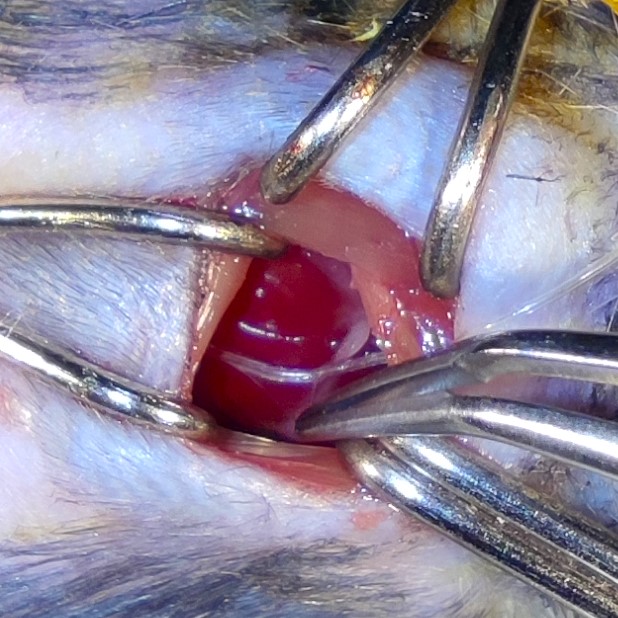

My research focuses on developing targeted cardiac drug-delivery strategies using the intrapericardial space as a novel and clinically relevant therapeutic access route. I established an intrapericardial catheter–based platform that enables direct, localized delivery of small molecules, biologics, nanoparticles, and cell-based therapies to the heart, allowing precise modulation of cardiac biology while minimizing systemic exposure.

This approach has gained rapid visibility following its initial publication, prompting multiple independent commentaries and underscoring strong interest from both clinical and basic research communities. Its early adoption highlights the platform’s novelty, translational potential, and relevance to cardiovascular therapeutics.

Building on this foundation, my work aims to expand this delivery system into a versatile preclinical pipeline for evaluating next-generation therapies targeting immune regulation, angiogenesis, fibrotic remodeling, ischemia/reperfusion injury, and pericardial inflammation in cardiovascular disease.

A key component of this effort is the use of the intrapericardial space as a distinct therapeutic compartment, enabling localized delivery of immunomodulatory, gene-targeting, and regenerative agents directly to the heart. This strategy reduces systemic exposure while enhancing mechanistic precision and translational relevance.